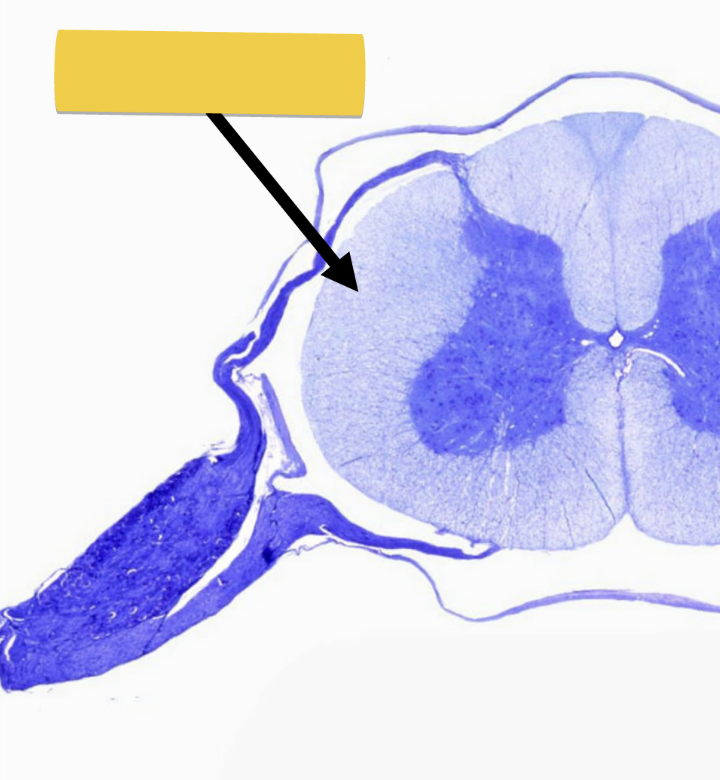

dorsal root/rootlets

enter/exit cord carrying sensory impulses

<p>enter/exit cord carrying sensory impulses</p>

ventral root/rootlets

enter/exit cord carrying motor impulses

<p>enter/exit cord carrying&nbsp;motor impulses</p>

dorsal root ganglion

contains cell bodies of sensory neurons

spinal nerve

short segment carrying ALL sensory and motor impulses at certain level of spinal cord

<p>short segment carrying ALL sensory and motor impulses at certain level of spinal cord</p>